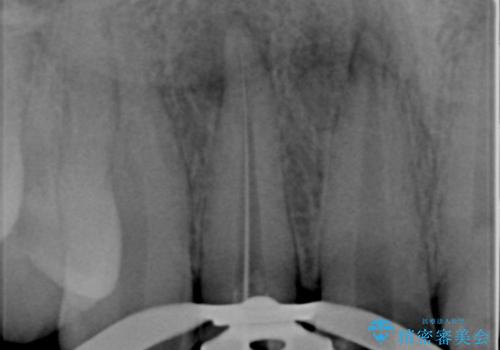

- 前歯の変色や形態を含む、見た目を改善したいと希望され来院されました。

視診・X線検査・歯周組織検査より下記のような問題が列挙され、長期的な予後を見込むために一つづつ問題の解決を計ります。

・不十分な根管治療 →マイクロスコープを用いる精密根管医療

・歯の変色 →ジルコニアクラウンの製作

・歯肉縁下カリエス →部分矯正による歯の挺出・歯周外科

歯の挺出を行ったことで歯ぐきの腫れも改善され、安定した歯周環境下でのセラミッククラウン治療を行うことができました。